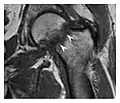

Proximal femoral fractures usually occur in osteoporotic patients, and their signs include subtle neck angulation, trabecular angulation, and subcapital impaction line. A frog-leg lateral view may be helpful if the greater trochanter is short enough. However, positioning can be difficult because of hip pain. In patients with strong suspicion of proximal femoral fracture and negative radiographs, MRI limited to coronal T1 W images and scintigraphy can be highly valuable (Figures 13 and 14). Such an option, with limited examination time, is cost-effective and allows reliable exclusion or confirmation of the diagnosis, preventing an unnecessary stay at the hospital or delayed treatment. Moreover, MRI helps to detect soft tissue abnormalities which are more frequently seen in femoral, acetabular, and pubic injuries than sacral lesions. Concomitant fractures are also frequently seen in typical pelvic sites.[1]

a

b

Figure 14: Subcapital insufficiency fracture in a 55-year-old man with a left hip pain without a history of trauma. Anteroposterior and Lauenstein view radiographs centered on the left hip do not show an obvious fracture line, but mild acetabular osteophytosis was noted consistent with hip osteoarthritis (not shown). (a) Coronal T1-weighted MRI shows a linear low-signal band through the femoral neck corresponding to a fracture line (arrowheads). (b) Bone scintigraphy shows focal uptake (arrow) corresponding to the fracture.[1]